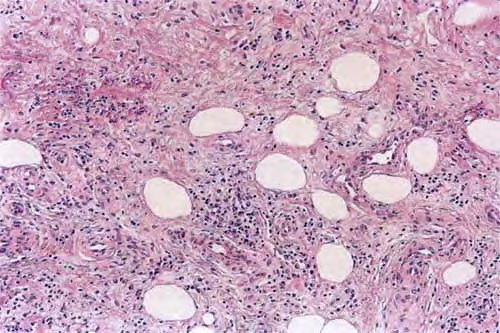

Traumatic panniculitis = التهاب السبلة الشحمية الرضي